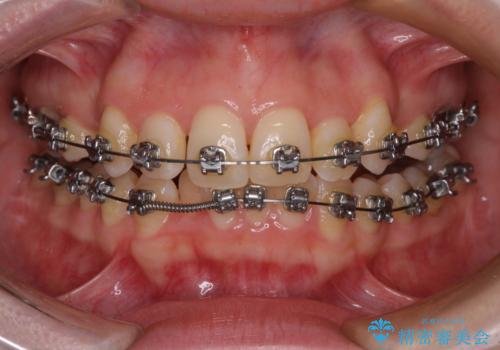

- 矯正装置

- メタルブラケット

上顎前歯部はデコボコが強く、歯を並べるためのスペースが不足しているため、左右の第一小臼歯を抜歯することとしました。

また、抜歯して確保したスペースが不足してしまうのを防ぐため、補助装置を併用しています。

補助装置を併用したおかげで、出っ歯になることなくスムーズに治療を終えることができました。